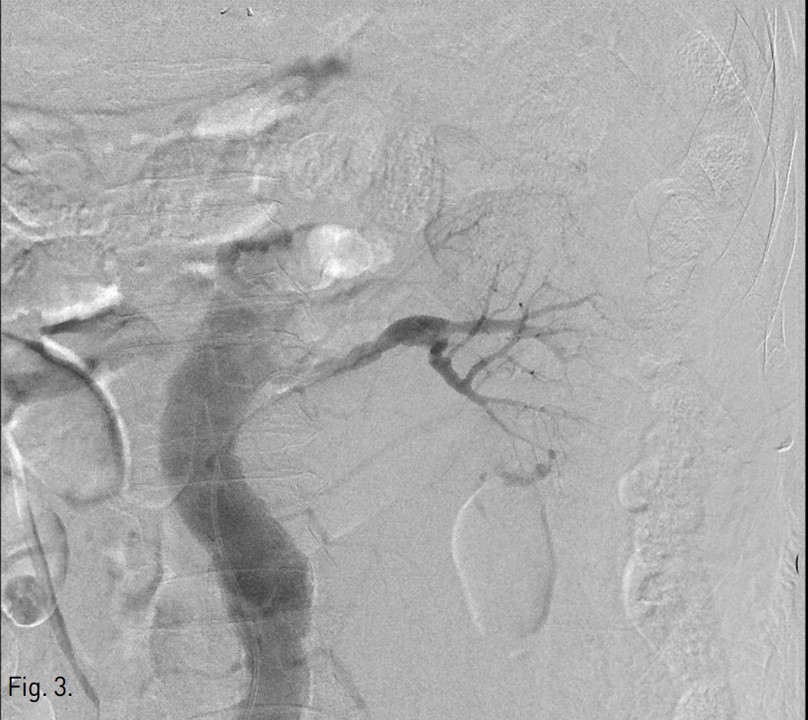

우측 총대퇴동맥을 천자하여, 5Fr sheath(Terumo, Tokyo, Japan)를 통해 5Fr Cobra catheter(Cook, Bloomington, USA)를 좌측 신동맥 기시부에 위치하여 혈관조영술을 시행하였다. 좌측 콩팥의 하극 부위 콩팥동맥 분지에서 조영제 누출이 있었다(Fig. 3). Microcatheter(Stride, Asahi Intecc co., Japan)로 출혈이 있는 신동맥 분지를 선택하여 microcoils (3x2mm, Tornado embolization microcoil, Cook, Bloominton, USA) 3개와 gelatin sponge particles (Gelfoam, Upjohn, Kalamazoo, MI, USA)을 이용하여 색전술을 시행하였다. 이후 시행한 혈관조영술에서 더 이상의 조영제 누출이 보이지 않아 시술을 종료하였다(Fig, 4). 이후 8개월 뒤 추적 전산화단층촬영에서 좌측 콩팥주위 혈종은 매우 크기가 감소하였다(Fig. 5).

Fig. 3.

Fig. 3. Left renal angiography shows contrast extravasation from the distal branch of left renal artery.